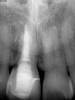

Plugging into digital workflows provides opportunities to integrate CAD/CAM technologies at every step of the treatment process for dental implants. In another example, a patient presented with a failing tooth No. 8 (Figure 6 and Figure 7). After discussing treatment options, the patient chose to forgo any treatment to address tooth and soft-tissue asymmetries and wanted to proceed with a dental implant-supported restoration without additional treatment. After integrated 3-dimensional planning, the tooth was extracted, and then an implant and the final custom CAD/CAM abutment (titanium base with zirconia supra-structure) were placed with a provisional restoration in the same visit (Figure 8 and Figure 9). Soft-tissue grafting was also done at the same visit to address the deficient buccal tissue height on No. 8 (Figure 10). At 3 months, the patient presented for the final restoration, with excellent healing around the implant (Figure 11) and soft-tissue healing guided by the custom abutment (Figure 12).

Fig 7. Preoperative radiograph showing previous endodontic therapy on tooth No. 8.

Figure 7